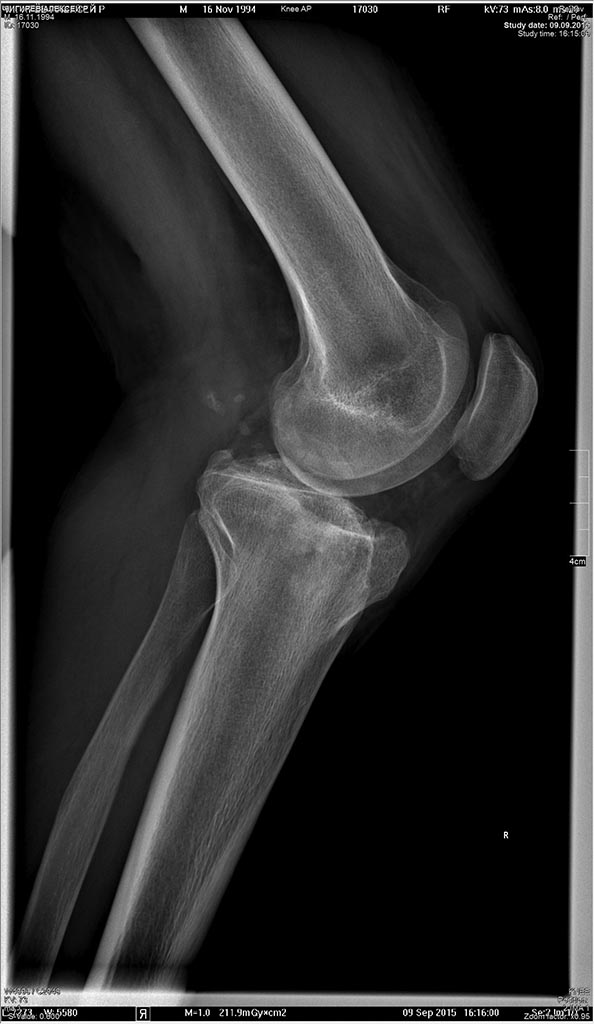

Пациент 21 г.

посттравматический гонартроз. Застарелое повреждение наружной боковой и

задней крестообразной связок. Посттравматическая нейропатия

малоберцового нерва.

Травма 3 года назад.

Вывих костей голени.

На момент осмотра: Жалобы на нестабильность в коленном суставе. Объем

движений в коленном суставе полный. Нестабильность наружно-задняя.

Р-гр в приложении.

Планируется первым этапом корригирующая остеотомия внутреннего

мыщелкабольшеберцовой кости  и восстановление наружной боковой

связки.При необходимости вторым этапом пластика ЗКС.